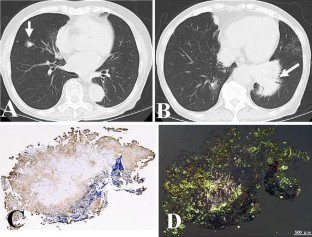

We report an unusual pathological finding, a large-sized bubbling appearance of the glomerular basement membrane (GBM), in a patient with pulmonary limited AL amyloidosis and a past history of lupus nephritis. The first renal biopsy specimen from 10 years ago, when systemic lupus erythematosus was diagnosed, demonstrated mild mesangial proliferation and subepithelial deposits (WHO classification: III + V). Light microscopy of the current biopsy using periodic acid methenamine silver (PAMS) stain demonstrated a large-sized bubbling appearance of the GBM; however, very weak immunoglobulin and complement deposition was observed in immunofluorescence studies. Routine electron microscopy demonstrated partial subendothelial expansion with electron-lucent materials, but no electron-dense deposits or amyloid fibrils. Electron microscopy with PAMS stain revealed electron-lucent endothelial scalloping, including some cellular components and microspheres in the GBM; however, it is not clear if these materials are derived from endothelial cells. One possibility is that these unique findings represent a recovery phase of lupus membranous nephritis; another is that these findings correspond to a new disease entity.

Fig. 1

The authors were supported by a grant from the Amyloidosis Research Committee of the Intractable Diseases Division in the Ministry of Health, Labour and Welfare of Japan. We thank Dr. M. Ueda and Dr. Y. Ando for their analysis of anti-λ antibody staining (Fig. 1c) and amyloid staining (Fig. 1d) in the pulmonary biopsy specimen.